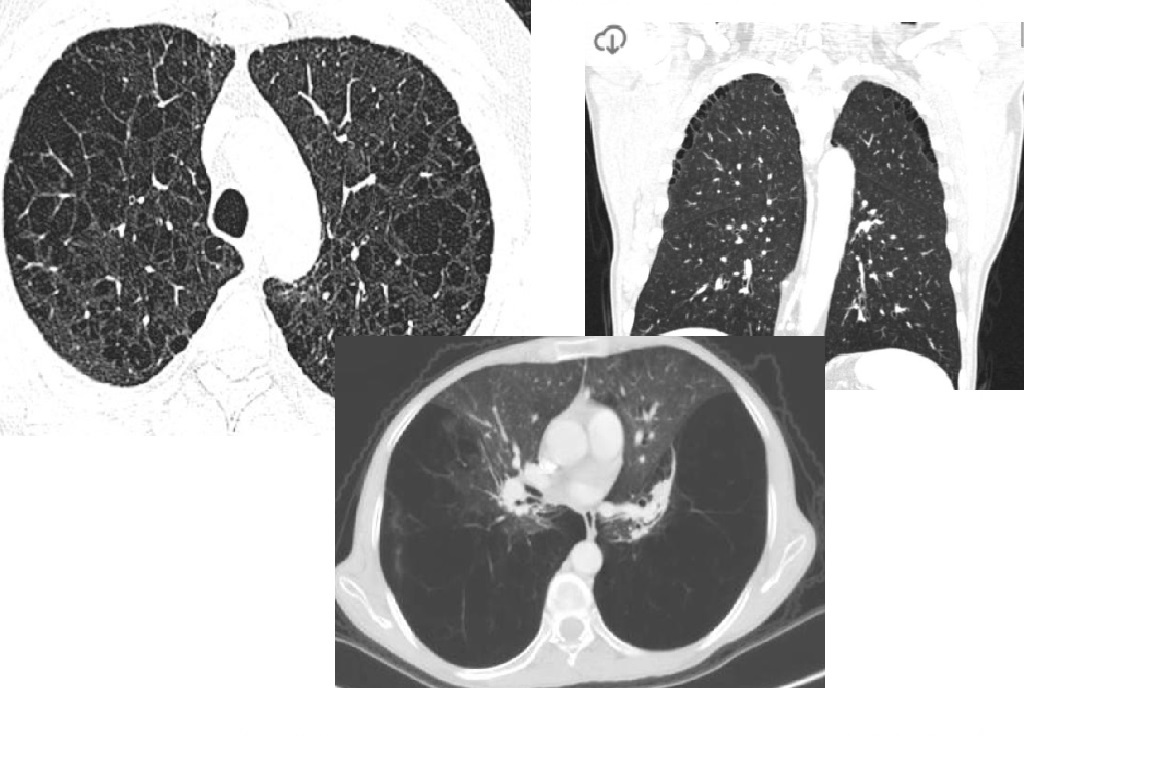

Lymphangioleiomyomatosis (LAM)

Diffuse no lobe predominant Thin walled cysts

Spontaneous PTX

Premenopausal women

NORMAL lung volumes

Chylous pleural effusions

increased lung volumes

Associated with tuberous sclerosis - 1/3rd have AMLs

Pulmonary Langerhans cell histiocytosis (PLCH)

Predominant upper lobes

bizarre-shaped thick pulmonary cysts

Smokers

Early stages of disease, 1-10mm nodules in mid/upper zone predominant

Effusions are rare

Sparing costophrenic angles